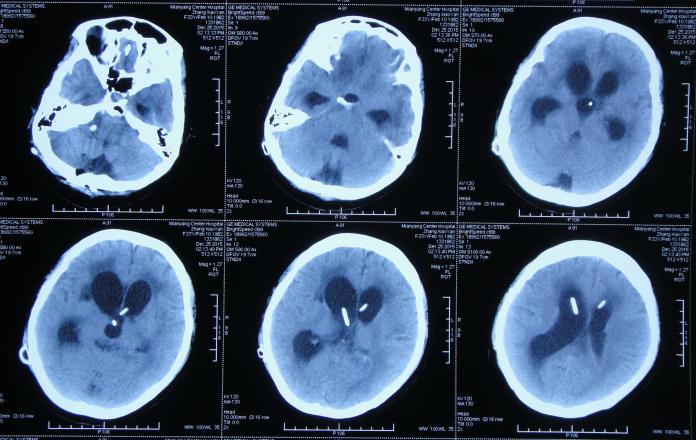

第1家医院治疗13天后即2015年8月16日,查头CT:双侧侧脑室,三脑室及四脑室扩张(图-4),且给予腰穿检查,提示颅压高(脑脊液检查结果不详),给予相关对症治疗。

图-4:2015年8月16日头部CT

第1家医院治疗16天后即2015年8月19日,间断头痛,腰穿颅内压仍高,查头部CT示脑室进一步扩张(图-5)。

图-5:2015年8月19日头部CT